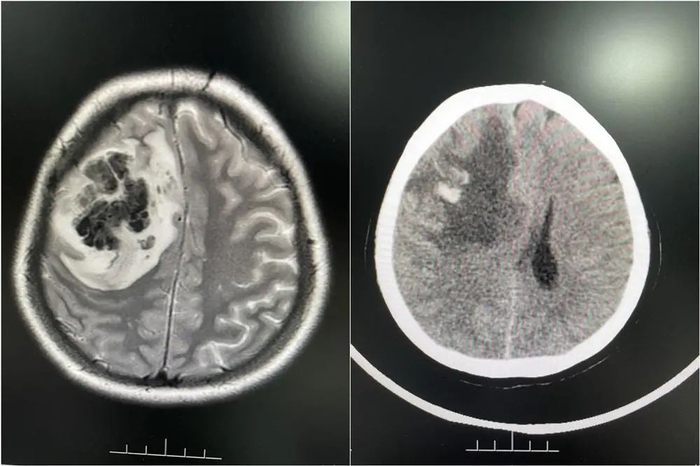

随后,婷婷在当地医院查出右侧额叶占位性病变合并出血,医生怀疑是脑肿瘤卒中。陈女士说:“婷婷当时已经昏迷不醒,都剃了头发准备手术。”为寻求进一步诊疗,2月底,家人陪同婷婷来到广东一家脑科医院。

医院接诊医生仔细分析后,发现婷婷颅内病变不是脑肿瘤。结合病史和相关影像资料,该院神经内一科副主任匡祖颖初步怀疑是颅内静脉窦血栓。进一步完善全脑血管造影,证实是颅内静脉窦血栓形成合并出血。